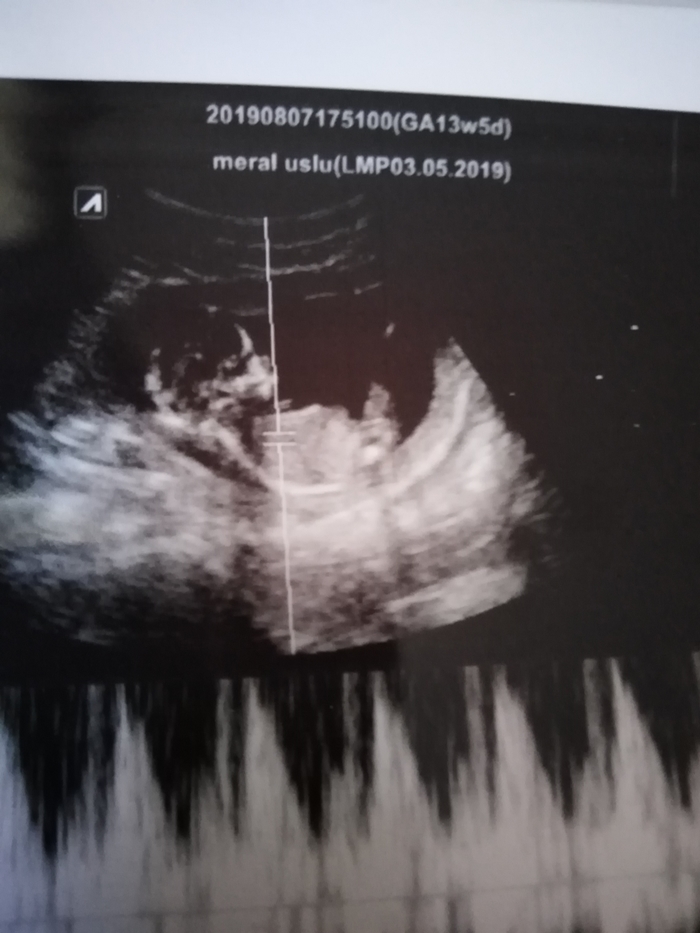

Ultrason sonucuna göre cinsiyet tahmini

Merhabalar gönderdiğim usg ye göre cinsiyet yorum yapar mısısnız

Selamlar malesef gönderdiğiniz resim sonuca ulaşmamız için yeteterli veri içermiyor. Lütfen aşağıdaki konumuzu inceleyerek ona göre resim atabilir misiniz ?